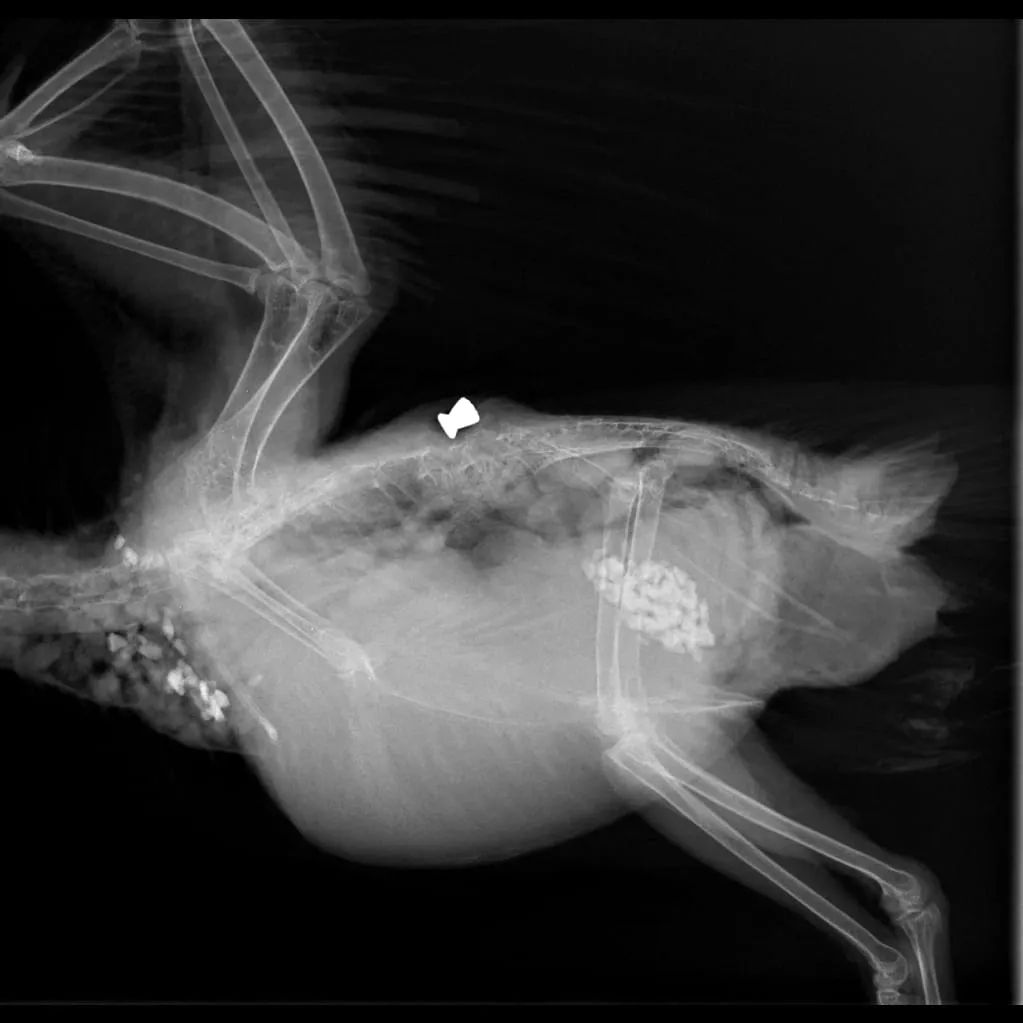

E' stato recuperato da una volontaria OIPA che ha poi fatto una staffetta per riuscire a farlo visitare da un veterinario specializzato, che in seguito ad una visita approfondita e ad una lastra ha constatato che qualcuno gli aveva sparato.

Le foto parlano da sole, un pallino conficcato nella spina dorsale l'aveva purtroppo paralizzato.